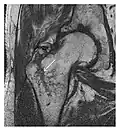

-

a -

b

Figure 7: Fatigue fracture of the talus in a 25-year-old male basketball player with right hind foot and ankle pain, without history of trauma, and a normal initial radiograph (not shown). (a) One-month followup lateral radiograph shows normal appearance. (b) Sagittal T1-weighted MRI shows an irregular fracture line (arrow) within an ill-defined area of hypointensity corresponding to bone marrow edema.[1]